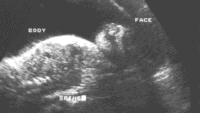

На ультразвуке, черепная коробка симметрично отсутствует. Рудиментарная мозговая ткань покрыта мембраной, а не костью (рис 1-2). Она, как было замечено, выступает над основанием черепа уже вначале второго триместра, и постепенно дегенерирует, пока наконец изображение головы полностью сглаживается позади лицевых структур. Внешний вид лица приобретает подобие лягушки с «выпученными» глазными яблоками (рис 3,4). Сопутствующее многоводие обычно развивается во втором триместре из-за отсутствия или неэффективного эмбрионального глотания (рис. 3). Часто наблюдается повышенная активность эмбриона. Рис.1-4. Сонографические ловушки в диагнозе анэнцефалии обычно возникают вокруг трудностей в визуализации при головном предлежании с глубоким положением головы. Дифференцирование анэнцефалии от серьезной микроцефалии или большого энцефалоцеле может также быть трудно, но при этих состояниях свод черепа всегда присутствует. Связанные с амнионом синдромы, ассоциированные с разрушением головного мозга, могут также имитировать анэнцефалию. Наконец, неопытный сонографист может путать мембрану с нормальным сводом черепа в раннем втором триместре. Поэтому, идентификация эмбриональной головы не исключает анэнцефалии.